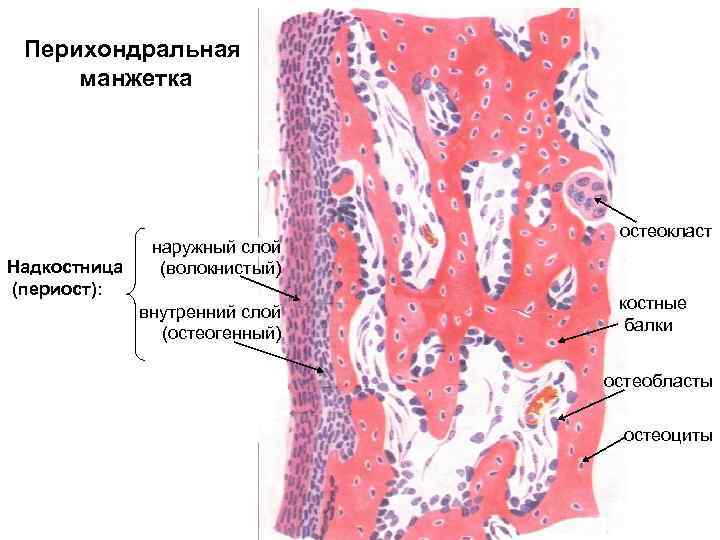

Структура грубоволокнистой костной ткани: наглядные примеры